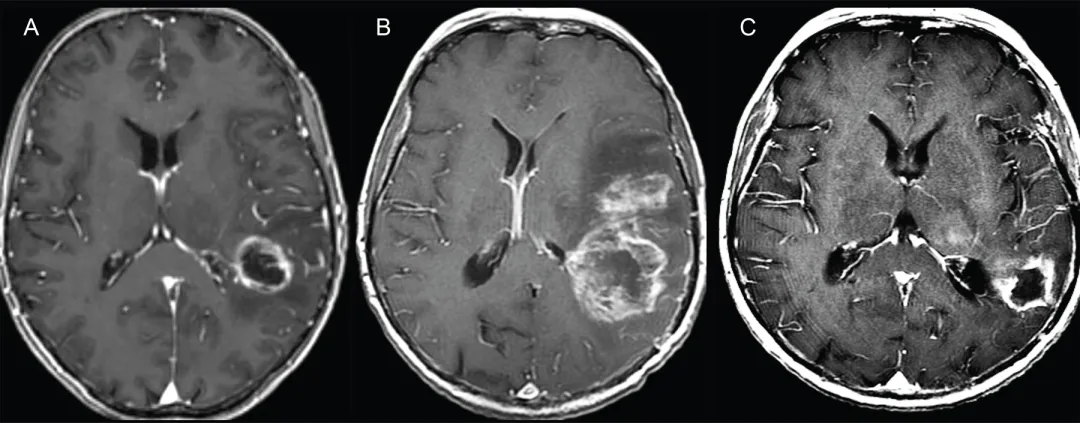

图1.假性进展典型病例

左侧额顶叶GBM轴位T1加权增强MRI图像:

A.活检后、放疗前图像显示左侧额叶后部脑室旁GBM

B.外照射放疗结束后1周图像显示占位效应显着加重,邻近脑室受压

C.放疗结束后3个月图像显示占位范围及占位效应显着消退